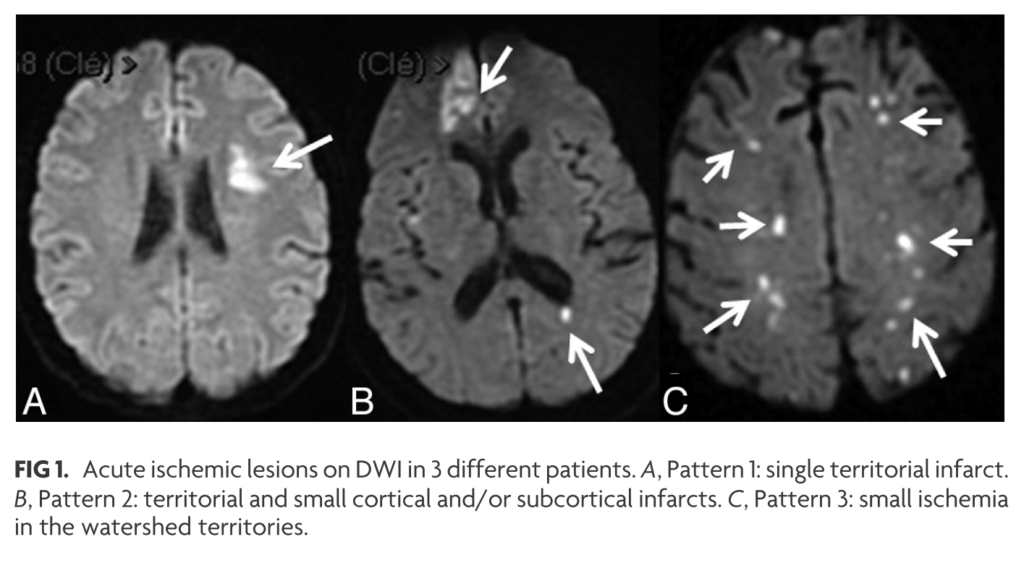

本棚にしまっていましたが使用しないので出品します。書き込みありません。非裁断です。「脳MRI 3 血管障害・腫瘍・感染症・他」高橋 昭喜定価: ¥ 12000#高橋昭喜 #高橋_昭喜 #本 #自然/医療・薬学・健康